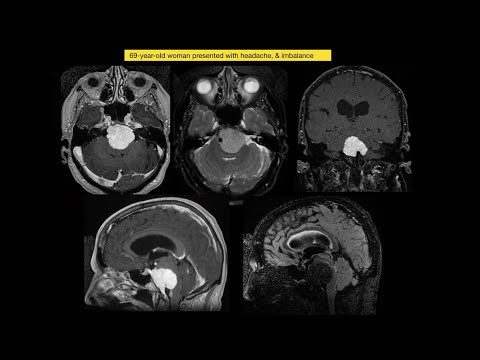

Hellow guys, Welcome to my website, and you are watching Treatment strategy of petroclival meningioma in the new millennium & our results. and this vIdeo is uploaded by Neurosurgical TV at 2021-12-14T10:28:28-08:00. We are pramote this video only for entertainment and educational perpose only. So, I hop you like our website.